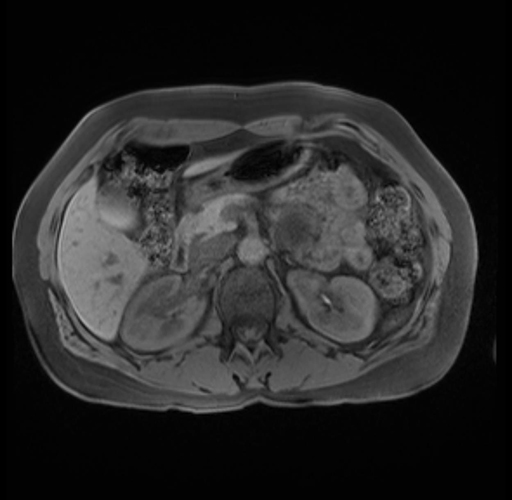

Imaging Analysis

Look through the patient's CT scan to identify any areas of concern for the necessary procedure.

Based on your CT findings, which issue(s) are present and would give reason for "planned slowing down moment(s)" in this case?

Considering a standard distal pancreatectomy procedure, what step(s) of the operation would you do differently in this case?